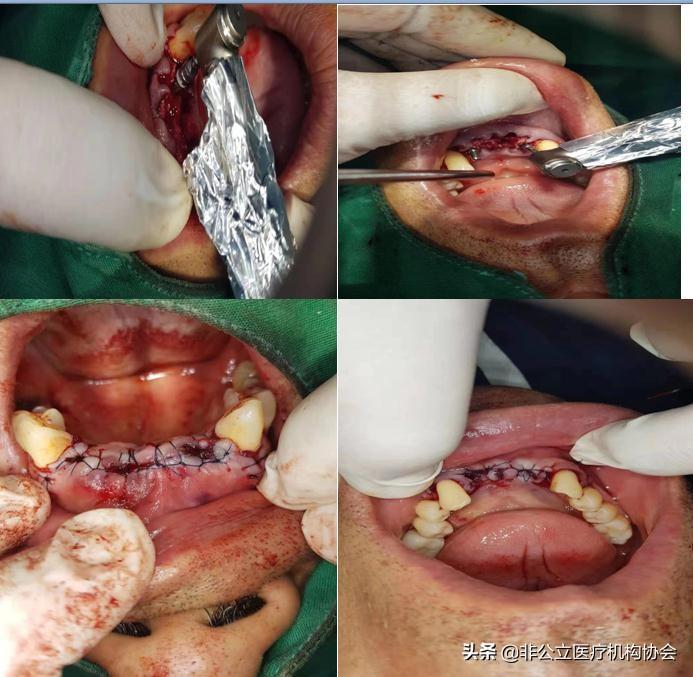

術(shù)前消毒(二)

患者術(shù)前的唇頰側(cè)觀(三)

患者術(shù)前病人的先拔牙(四)

新技術(shù)離心機抽血形成骨粉作用。

人工種植牙過程,很簡單,就要拔除牙齒一樣的。